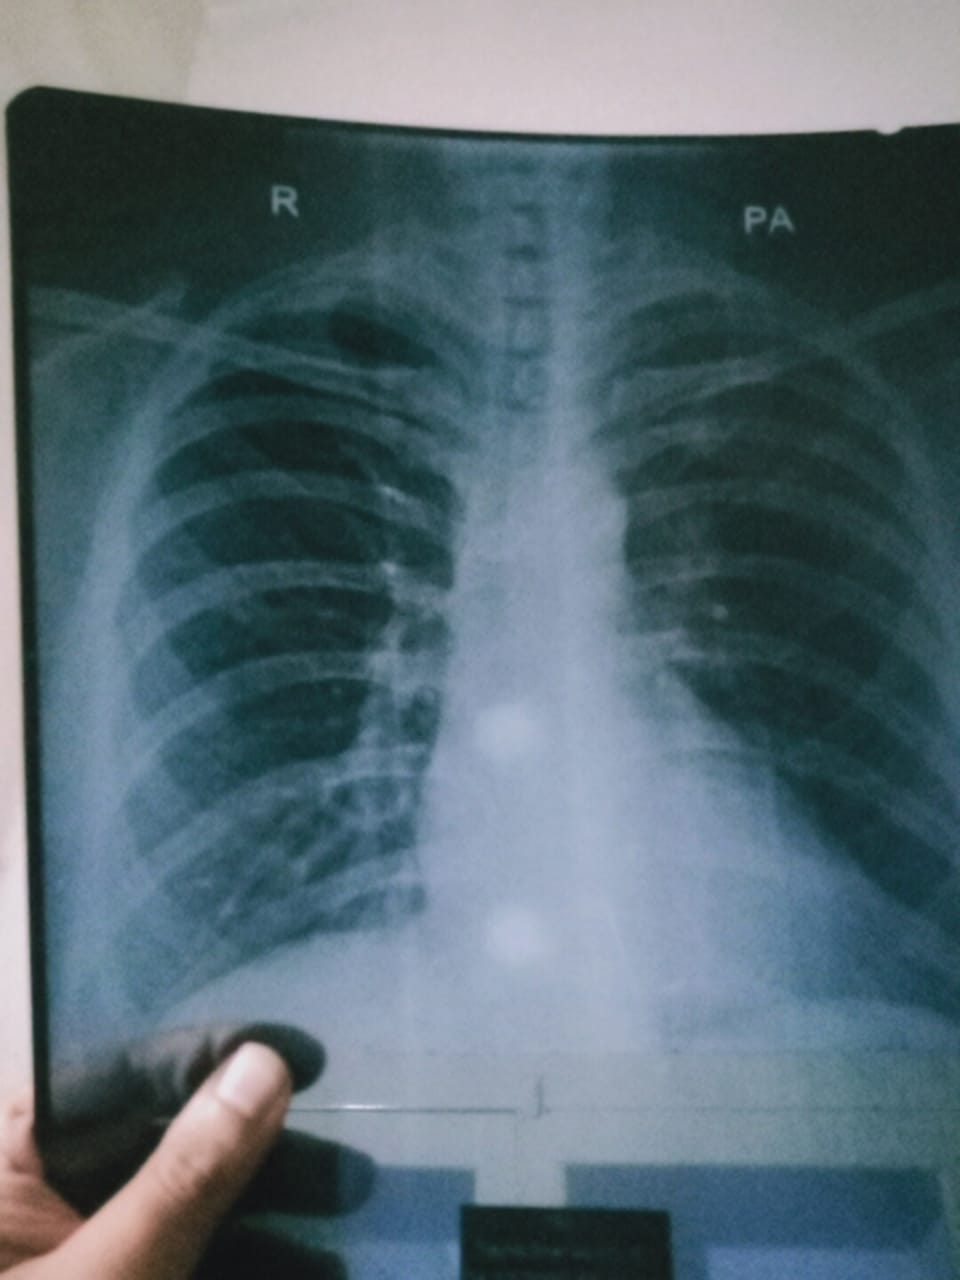

Asking for Mother, Female, 67 years old, Lahore My mother have an episode of haemoptysis in january 2019. Findings are:- Cystic changes in RUL , CXR Infiltrate seen on RUL , No pleural effusion, no honey combing structure, Patch consolidation seen on RUL ,CT Scan. IGE Levels were :121 Spirometry tets were perfect. Treatemnt she got is cefipime and tranexamic acid with cleniccla and auttum. But all of sudden as on 2nd Dec 2020 she got second epsiode of haemoptysis, slightly lighter than first she gets is moxyfloxacin tablet and tranexamic acid tablet with herbal cough syrup for seven she is fine. what approach or path should we take for treatment it so ething to worry or is just pneumonia. Regards.